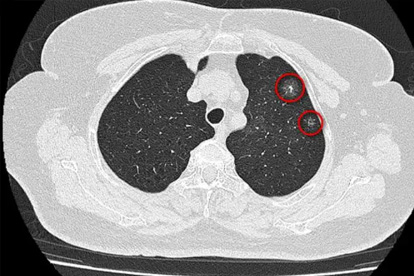

1、低剂量CT检查

相比普通胸片,能发现小至2毫米的肺部结节。建议高危人群每年做一次。